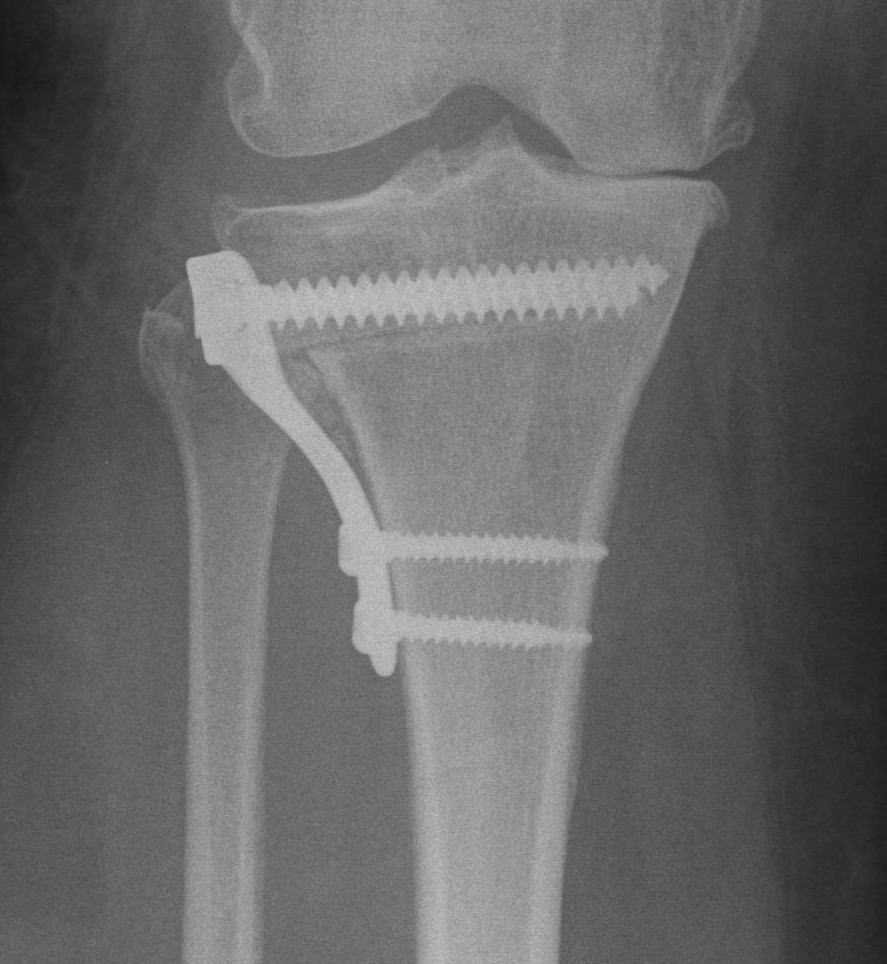

Stabilise osteotomy with plate